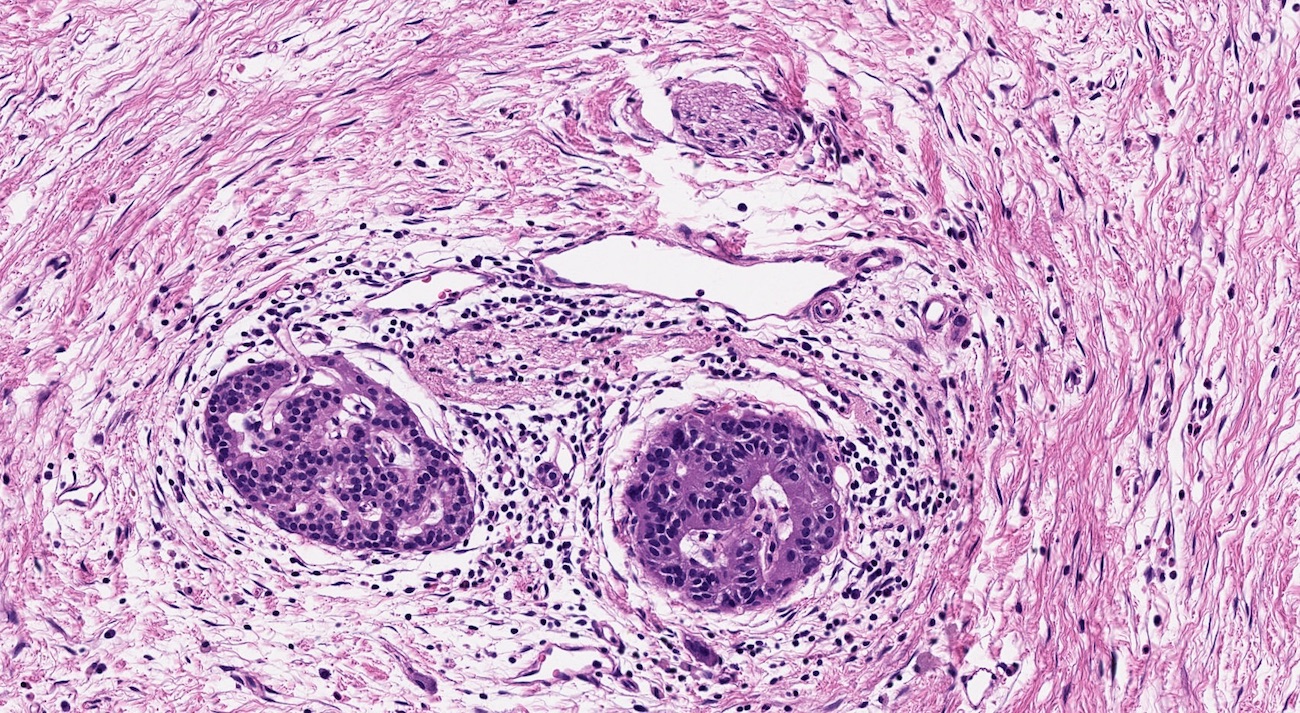

Microscopic (histologic) description

- Triad of cardinal features: fibrosis, loss of acinar tissue, duct changes (Pancreatology 2020;20:586)

- Fibrosis is initially perilobular; during disease progression, it involves the pancreatic lobular units, eventually replacing the acinar parenchyma (so called intralobular fibrosis)

- Acinar tissue may be replaced by fibrosis or fatty tissue; the latter process (lipomatous atrophy) is more frequently seen in hereditary pancreatitis (Pathologica 2020;112:197)

- Loss of acinar tissue predates that of pancreatic islets, which are often seen isolated in fibrosis or fatty tissue in advanced cases

- Ductal changes include distortion of ductal profiles, ectasia, presence of intraluminal concretions of amorphous material (so called protein plugs), squamous metaplasia, intraductal calcification

- Foci of low and high grade pancreatic intraepithelial neoplasia (PanIN) may be encountered

- Foci of periductal chronic inflammation and fat necrosis represent a common finding

- Pseudocysts lined by granulation tissue are common in alcoholic chronic pancreatitis

- Paraduodenal pancreatitis shows Brunner gland hyperplasia, myofibroblastic proliferation in the duodenal wall, cysts lined by cuboidal ductal epithelium, which may be replaced by granulation tissue; multinucleated giant cells may be found (Cytopathology 2015;26:122)

Microscopic (histologic) images